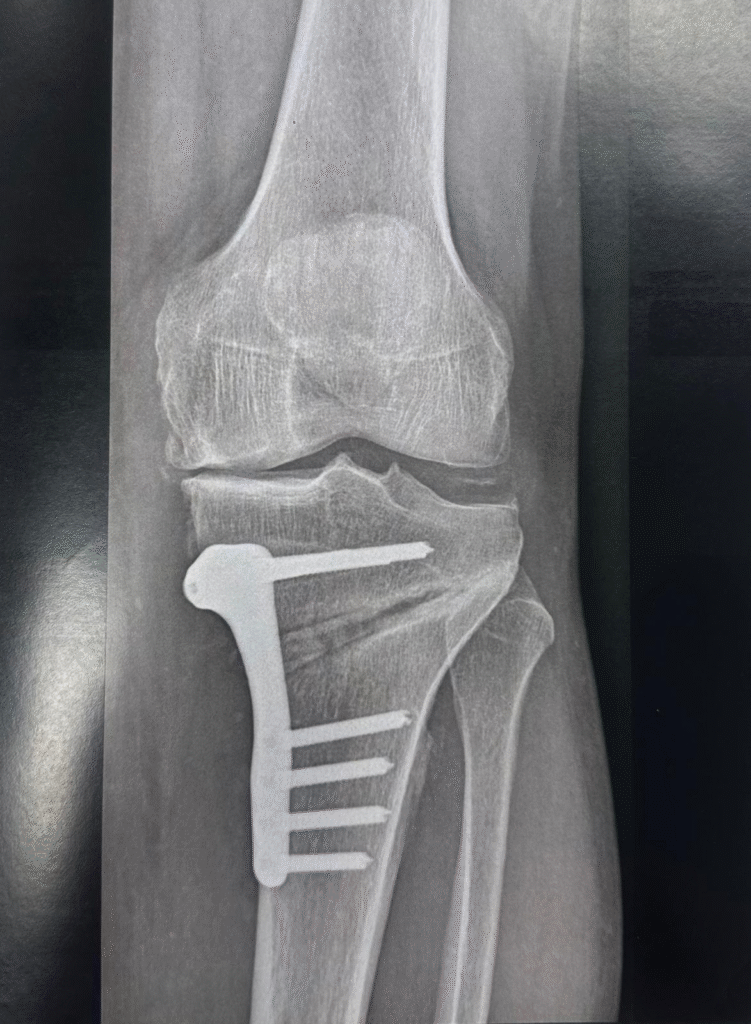

Ostéotomie tibial

Le principe : Restaurer un axe mécanique normal du membre inférieur pour optimiser la répartitions des contraintes sur le genou de manière à arrêter l’évolution de l’arthrose (Ostéotomie curative) ou à ralentir cette évolution (Ostéotomie palliative).

L’ostéotomie du genou est une intervention chirurgicale qui consiste à modifier l’alignement de l’articulation du genou en retaurant un axe mécanique normal Elle est souvent réalisée pour optimiser la repartition des contraintesen redistribuant le poids sur le genou afin de réduire la douleur et améliorer la fonction. Cette procédure peut impliquer la coupe et le réalignement du fémur ou du tibia.

L’ostéotomie peut être une option pour les patients qui ne répondent pas bien aux traitements conservateurs, comme la physiothérapie ou les médicaments. Elle peut également être envisagée chez les patients plus jeunes qui souhaitent éviter ou retarder une prothèse de genou.

Le principe d'une ostéotomie du genou

Restaurer un axe mécanique normal du membre inférieur pour optimiser la répartitions des contraintes sur le genou de manière à arrêter l’évolution de l’arthrose (Ostéotomie curative) ou à ralentir cette évolution (Ostéotomie palliative).

L’ostéotomie du genou est une intervention chirurgicale qui consiste à modifier l’alignement de l’articulation du genou en restaurant un axe mécanique normal Elle est souvent réalisée pour optimiser la répartition des contraintes en distribuant le poids sur le genou afin de réduire la douleur et améliorer la fonction. Cette procédure peut impliquer la coupe et le réalignement du fémur ou du tibia.

La réalisation :

L’intervention se réalise la plupart du temps sous anesthésie loco-régionale

Le chirurgien, après planification radiologique, va réaliser une fracture du haut du tibia ou du bas du fémur.

Des plaques d’ostéotomie sur mesure ont connu un essor important ces dernières années.

La déformation préopératoire et le résultat postopératoire désiré sont planifiés à l’aide de scanner pré-opératoire: Ainsi chaque patient bénéficie d’une plaque sur mesure, adaptée à son cas, ce qui facilite le geste opératoire.

La contention de la fracture va nécessiter la pose d’une plaque avec parfois du temps une greffe osseuse. Un drainage pour évacuer l’hématome est éventuellement mis en place.